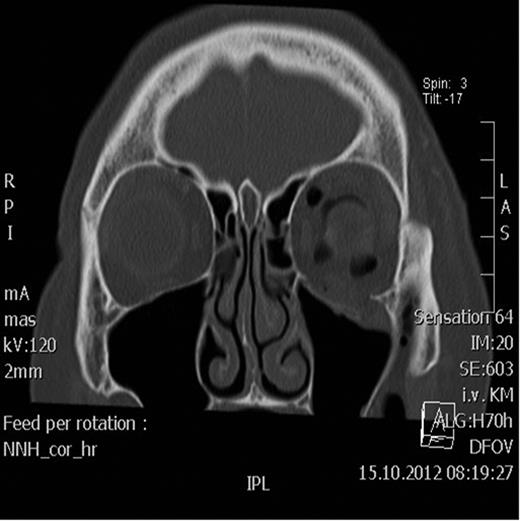

Postoperative axial CT scan showing normal position of the bulbus.

Two days after surgery, the patient was discharged with restored visual acuity and continuing resolution of the left periorbital swelling and proptosis.